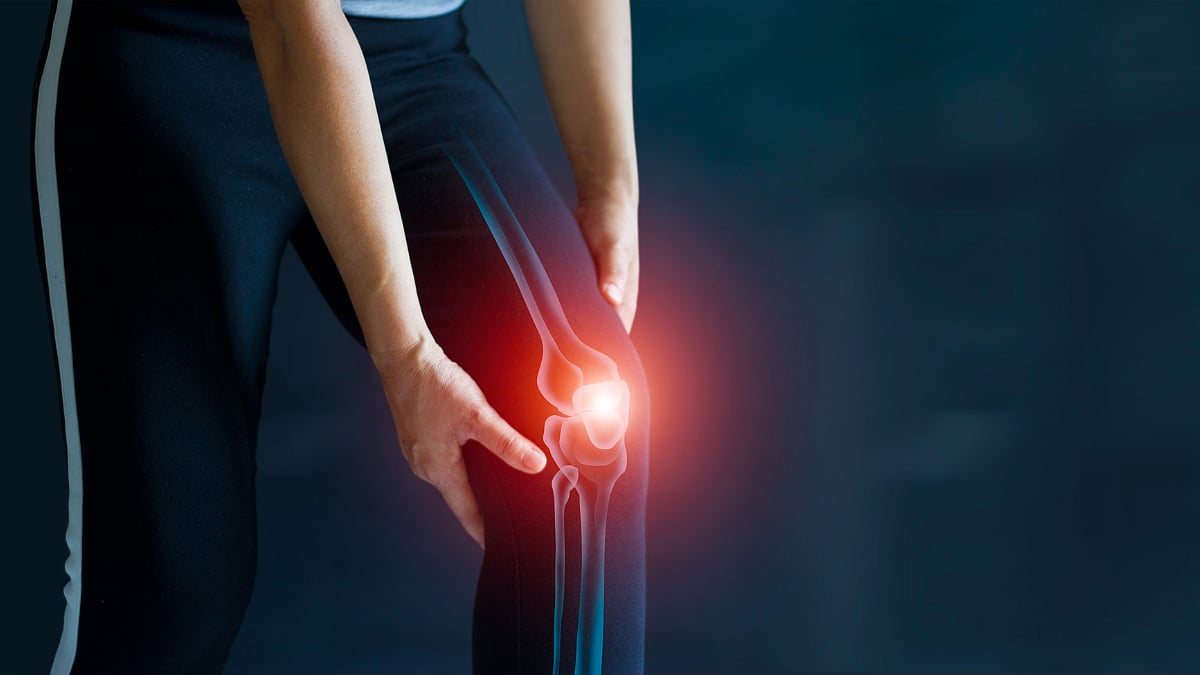

About Arthritis

When you suffer from arthritis, you face inflammation and swelling in the joint(s). It can cause stiffness and pain that grows with time. Types of arthritis with individual impacts on the joints include rheumatoid arthritis, osteoarthritis, fibromyalgia, lupus, and gout.

The causes include wear and tear of the joints due to age or injury, overweight impact, genetic factors, gender, infections, and even occupational factors. Apart from inflammation, stiffness, and swelling of the joints, the symptoms include tenderness, warmth around the joints, tiredness, limited motion, and even fever.

In Ayurveda, arthritis comes under Sandhivata. It is an ailment caused by Vata Dosha imbalance. This Dosha is associated with dryness, motion, and corrosion. Certain causes and age worsen the Vata and result in arthritis-related troubles. The other two Doshas, too, can be behind other types.